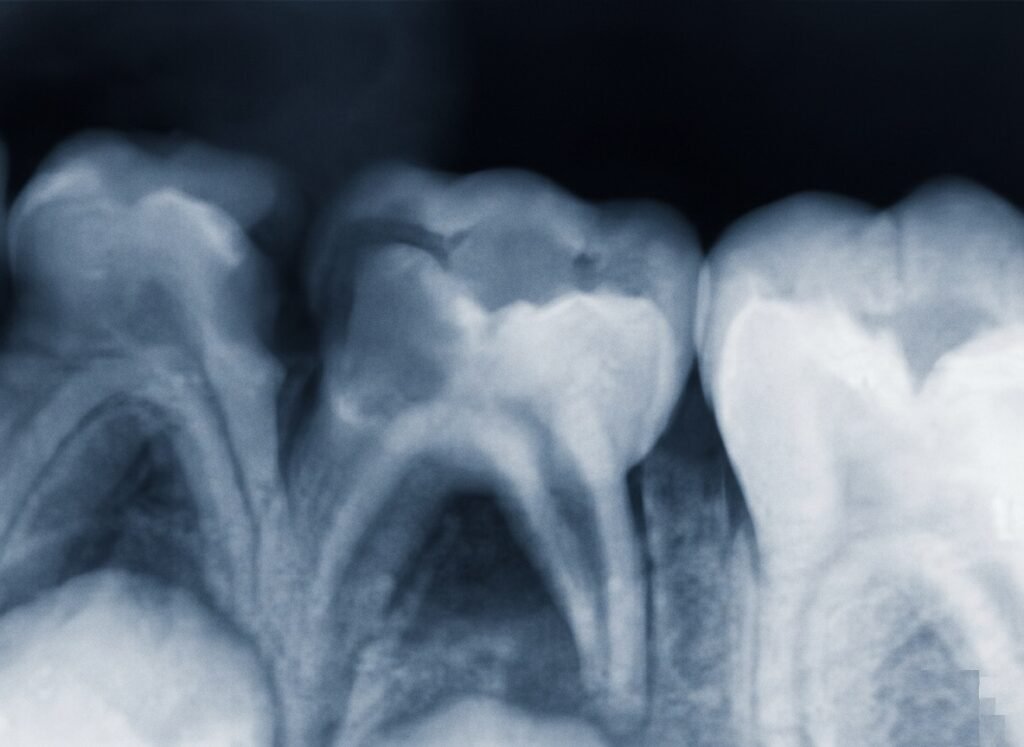

Diagnostic radiologique :

- Il est aisé, il y a disparition complète de l’architecture de l’os inter-radiculaire.

Signes radiologiques :

- Permettent d’établir le diagnostic, l’absence de radio-opacité de l’os alvéolaire inter-radiculaire et inter-dentaire signe l’étendue de la lésion.